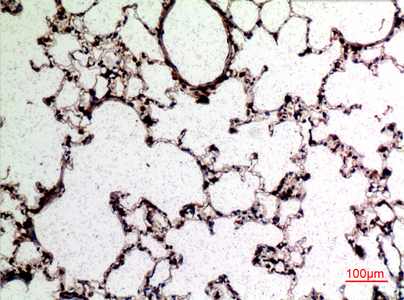

Immunohistochemistry analysis of paraffin-embedded rat lung using CD62L antibody.High-pressure and temperature Sodium Citrate pH 6.0 was used for antigen retrieval. |

Immunohistochemistry analysis of paraffin-embedded rat lung using CD62L antibody. High-pressure and temperature Sodium Citrate pH 6.0 was used for antigen retrieval. |